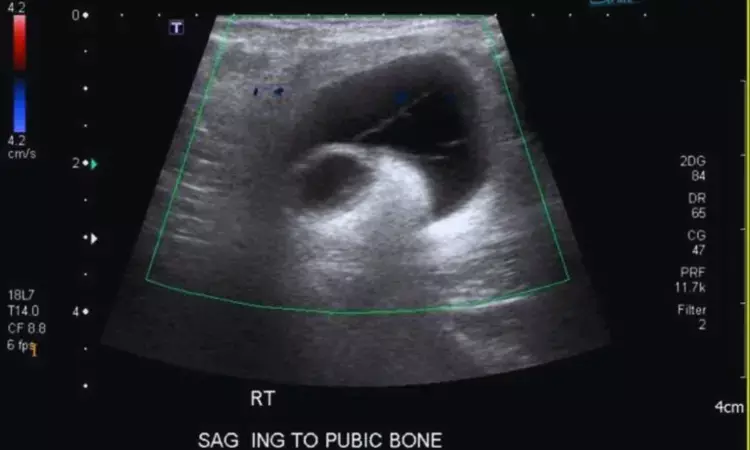

Meshoma: Rare Late Complication of Inguinal Hernia Detectable by Ultrasound — A Case Report

Italy: Meshoma is an uncommon but potentially serious late complication of inguinal hernia repair. Ultrasound serves as a valuable first-line imaging tool, enabling direct visualization of mesh folding and related fistulous tracts, thus aiding timely surgical management. A recent case report published in the Journal of Ultrasound by Giulio Cocco and colleagues highlights the critical role of ultrasound in diagnosing this rare but clinically significant condition.